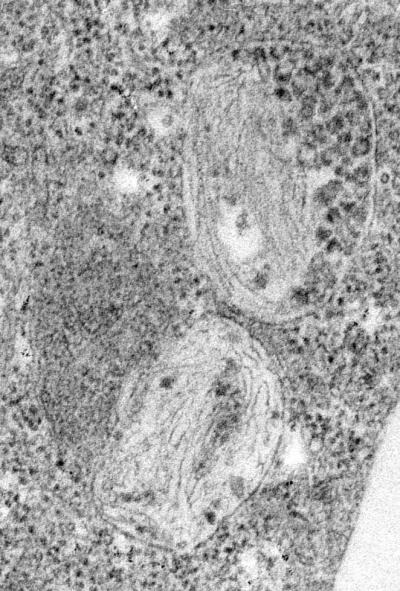

Before the fibers are laid down, the researchers found in the Developmental Cell study that Pmel17 passes through a series of compartments called endosomes, much the way proteins that are tagged for degradation do. They determined that this process also happens in non-pigment cells. This discovery indicates that sorting is not a melanocyte-specific process; the sorting phenomenon is a general one.

Other researchers have found that the Alzheimer's precursor protein, the prion protein (responsible for Creuztfeldt-Jakob's Disease, Mad Cow disease, and Kuru), and the precursors for several familial amyloid diseases all pass through one type of endosome. "This may be a general property of a class of amyloids – and the fact that the process happens in non-pigment cells means that it can also happen in neurons or epithelial cells where these amyloids cause problems," says Marks.